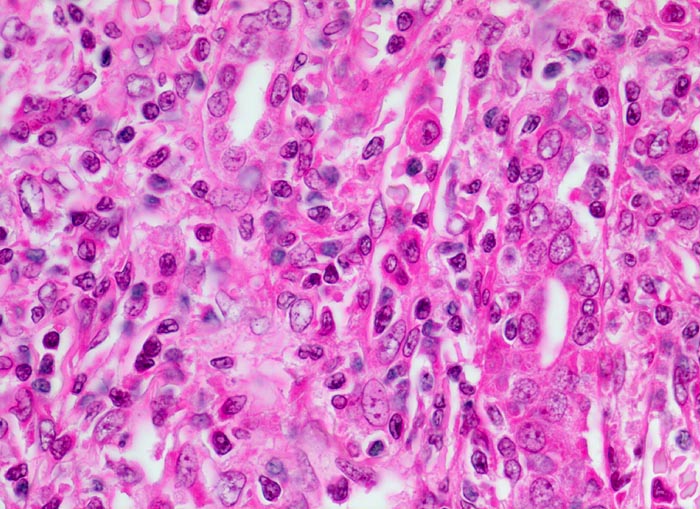

• Akute Abstossung (vorliegendes Präparat):

Typischerweise innert 1 bis 5 Wochen (meist innerhalb der ersten 3 Monate, kann aber jederzeit auftreten) nach Transplantation. Es handelt sich in erster Linie um einen zellvermittelten Prozess mit antigenspezifischer Immunantwort bei Histoinkompatibilität zwischen Spender und Empfänger (Coombs-Typ IV). Bei einem Grossteil der akuten Abstossungen mit Gefässbefall (Endarteritis) und/oder Transplantat-Glomerulitis sind gleichzeitig Antikörper gegen HLA-Antigene nachweisbar. Bei den meisten akuten Abstossungsreaktionen besteht ausschliesslich eine tubulo-interstitielle Entzündung mit Lymphozyten, Histiozyten und später Plasmazellen. Der Prozess ist heute meist reversibel. Histologisch unterscheidet man eine akute tubulointerstitielle, eine vaskuläre, selten eine glomeruläre Abstossung und Mischformen.

Morphologische Merkmale:

• Grosse Biopsie aus Nierenmark und -rinde, letztere mit 13 Glomeruli, alle mit normalem Zell- und Matrixgehalt sowie zarten Kapillarschlingen

• Tubulärer Apparat der Rinde mit ödematös verbreitertem und herdförmig dicht lymphohistiozytär durchsetztem Interstitium

• Vereinzelt Lymphozyten im Tubulusepithel (Tubulitis)

• Eine von 6 grossen bzw. mittelgrossen Interlobulararterien mit segmental verbreiterter, fibrosierter Intima mit Myofibroblasten und mit subendothelial gelegenen Leukozyten (Endothelialitis)